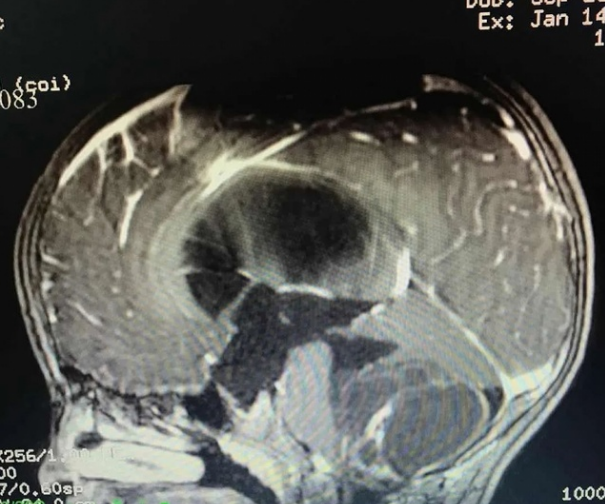

42岁的林女士(化名)因头痛眩晕、四肢麻木,检查发现脑干及颈髓腹侧胆脂瘤。日前,南方医科大学中西医结合医院神经外科团队为其手术,顺利切除了颅内肿瘤。术后,林女士恢复良好,语言、肢体功..

疫情期间,42岁的潮汕商人林女士因周身乏力、头疼眩晕且心跳加速,伴有四肢发抖、麻木、手脚出汗在当地医院检查发现脑干及颈髓腹侧占位性病变,转至南方医科大学中西医结合医院求医。